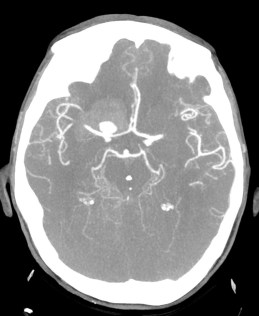

Se decide realizar Angio-TC.

Estamos ante una Hemorragia Subaracnoidea por rotura aneurismática.

Angiografía- TC: Se basa en la TC de cortes helicoidales. Aunque implica radiación para el paciente y requiere administración de contraste iodado intra-venoso (no requiere cateterización arterial), el hecho de que posea gran disponibilidad y sea una técnica rápida y fácil de llevar a cabo en pacientes enfermos, hace que se use como prueba de primera línea. Se puede realizar con cortes de 1 mm y realizaremos reconstrucciones para obtener imágenes como las de una angiografía (cine + MIP).